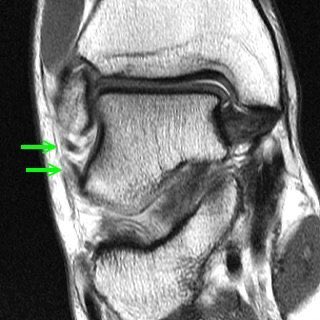

٣- أشعة الرنين المغناطيسي MRI ويتحدد بعد الفحص والكشف السريري